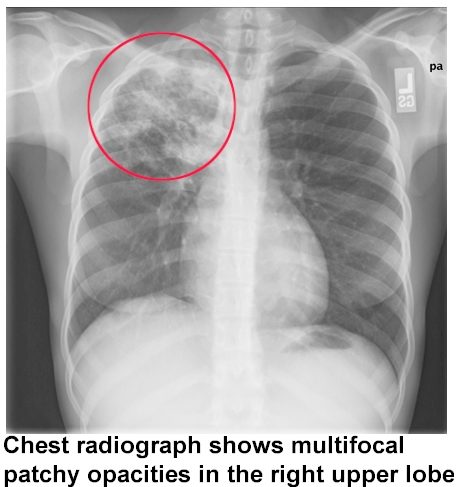

Radiological Findings of Pulmonary TB:

1/ Patchy opacity in the upper lobes (apex) of the lung , near the hilar area (hilar lymphadenopathy is seen) or even any other area in the lung field.

2/ Sometimes, Cavitation and lung collapse are also seen.